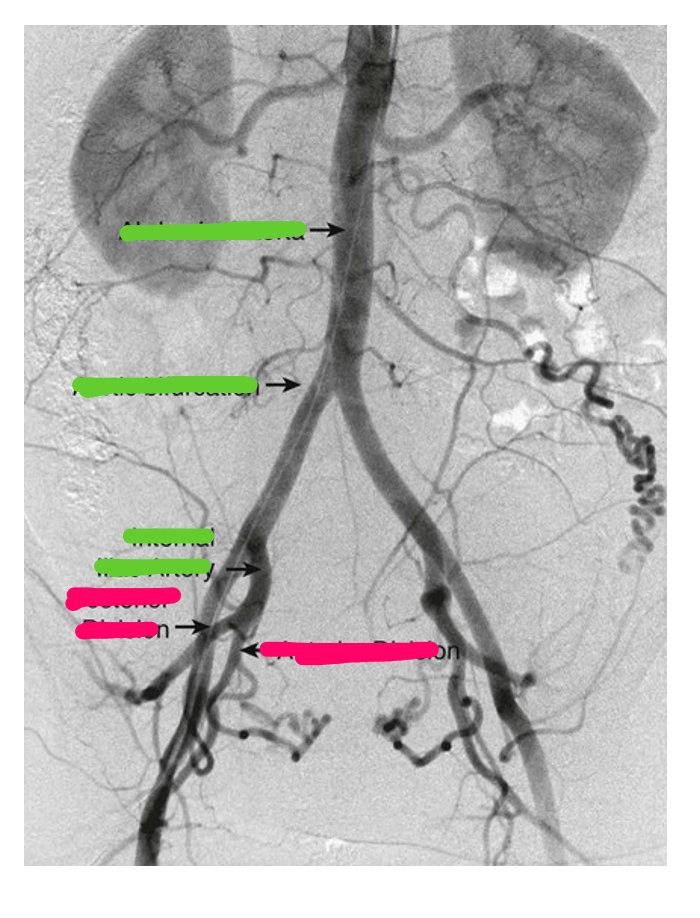

Complete the blanks & what imaging modality is this?

Female pelvic arteriogram

Imaging modality